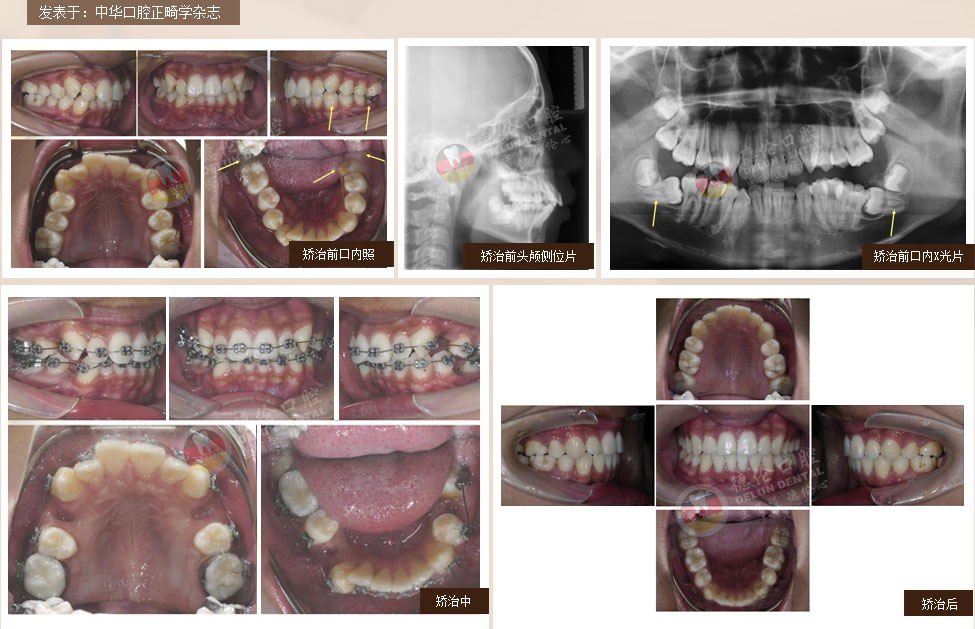

• 男:17歲

癥狀:下頜右側(cè)第二、第三磨牙水平阻生,下頜左側(cè)第三磨牙水平阻生

矯治方法:下頜拔除兩顆第三磨牙(智慧齒)